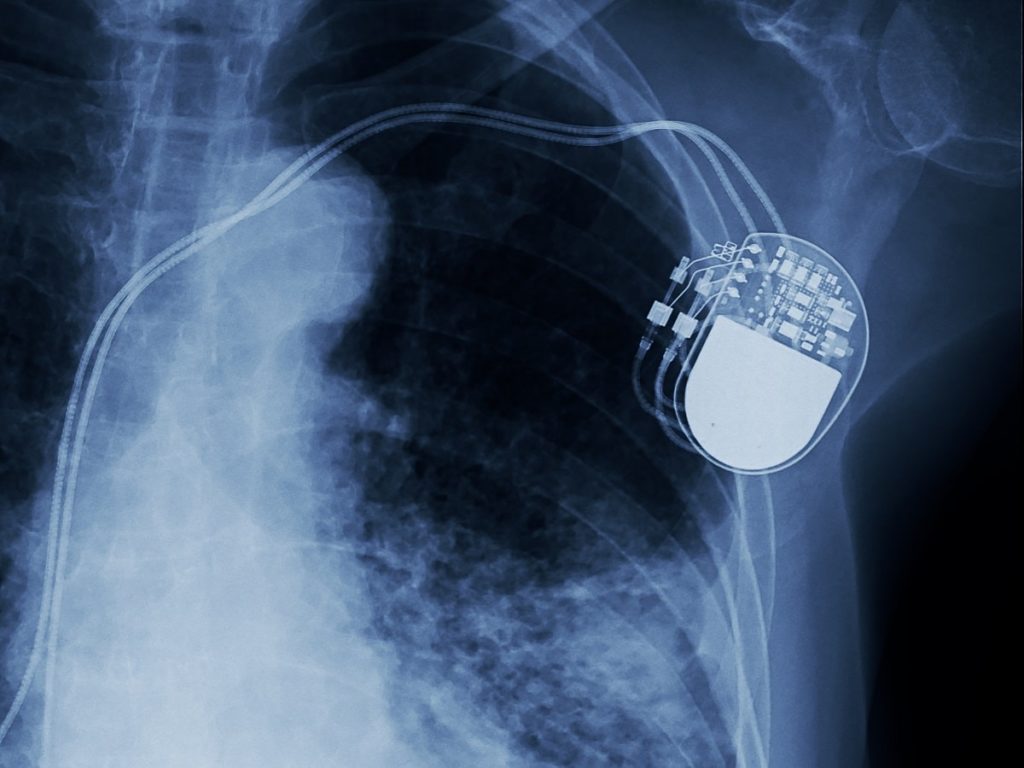

- Cubierta de marcapasos hecha de aliados de titanio.

– Para mejorar la función de algunos órganos: marcapasos cardíaco, lentes intraoculares, aparatos auditivos.